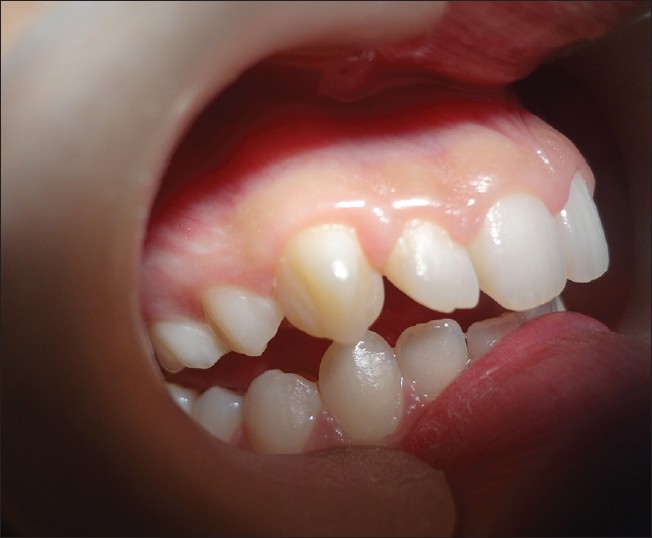

Facial talon cusp on permanent maxillary canine: A rare dental anomaly

p. 324

Seema Thakur, Reecha Gupta, Narbir S Thakur, Mohit Gupta

DOI

:10.4103/2278-9626.116004

Talon cusp is a rare form of developmental anomaly characterized by cusp like projections, usually presenting on palatal and lingual surface of the anterior teeth. Maxillary lateral incisor is most often affected followed by maxillary central incisor. This developmental anomaly is rare on the facial surfaces and very few cases have been reported. When it occurs, the effects are mainly aesthetic and functional and so early detection and treatment is essential in its management to avoid complications. An unusual case of talon cusp on the facial aspect of maxillary canine is reported. The chief complaint of the patient was impaired aesthetics. Aesthetic correction was There is only one reported case of facial talon cusp on maxillary canine till date. This case reports a very rare form of such anomaly along with management.